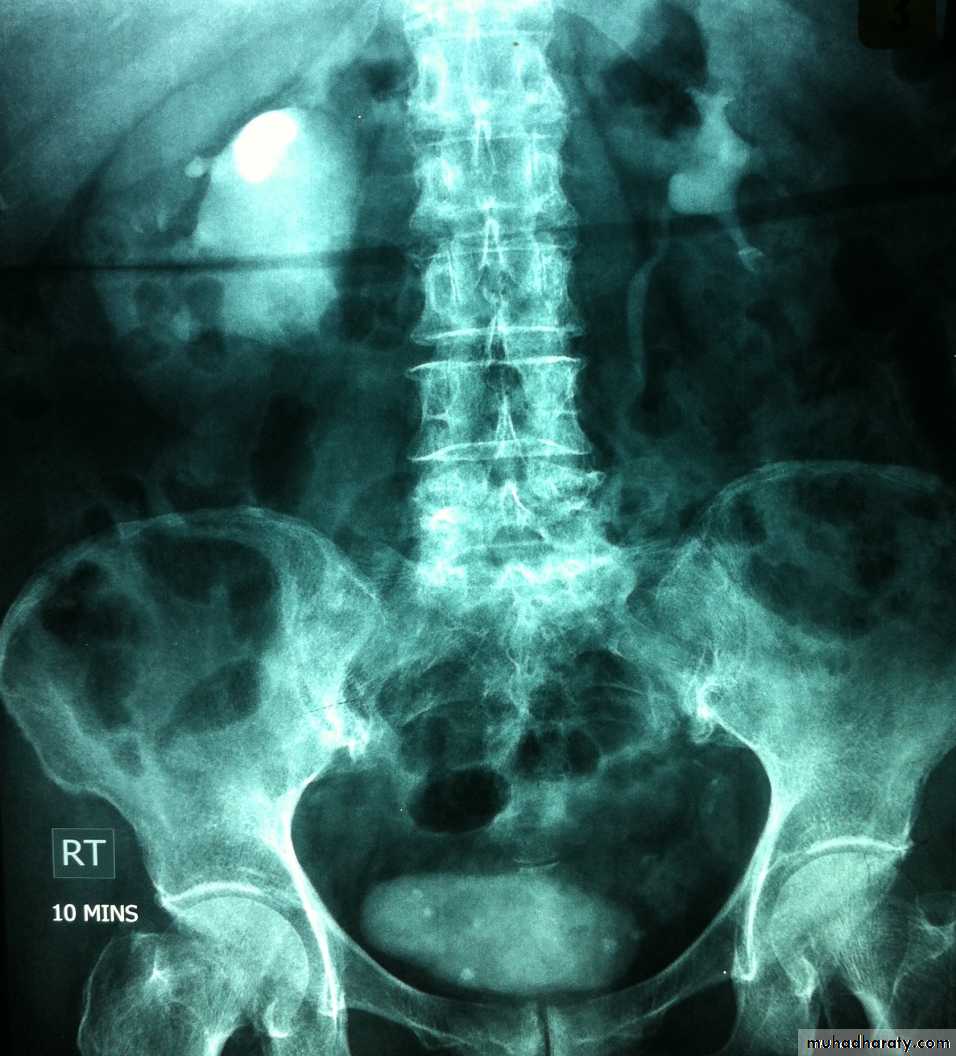

Horse shoe kidney :-*lower poles fused *low positioned kidneys *parallel to spines.*malrotated medially